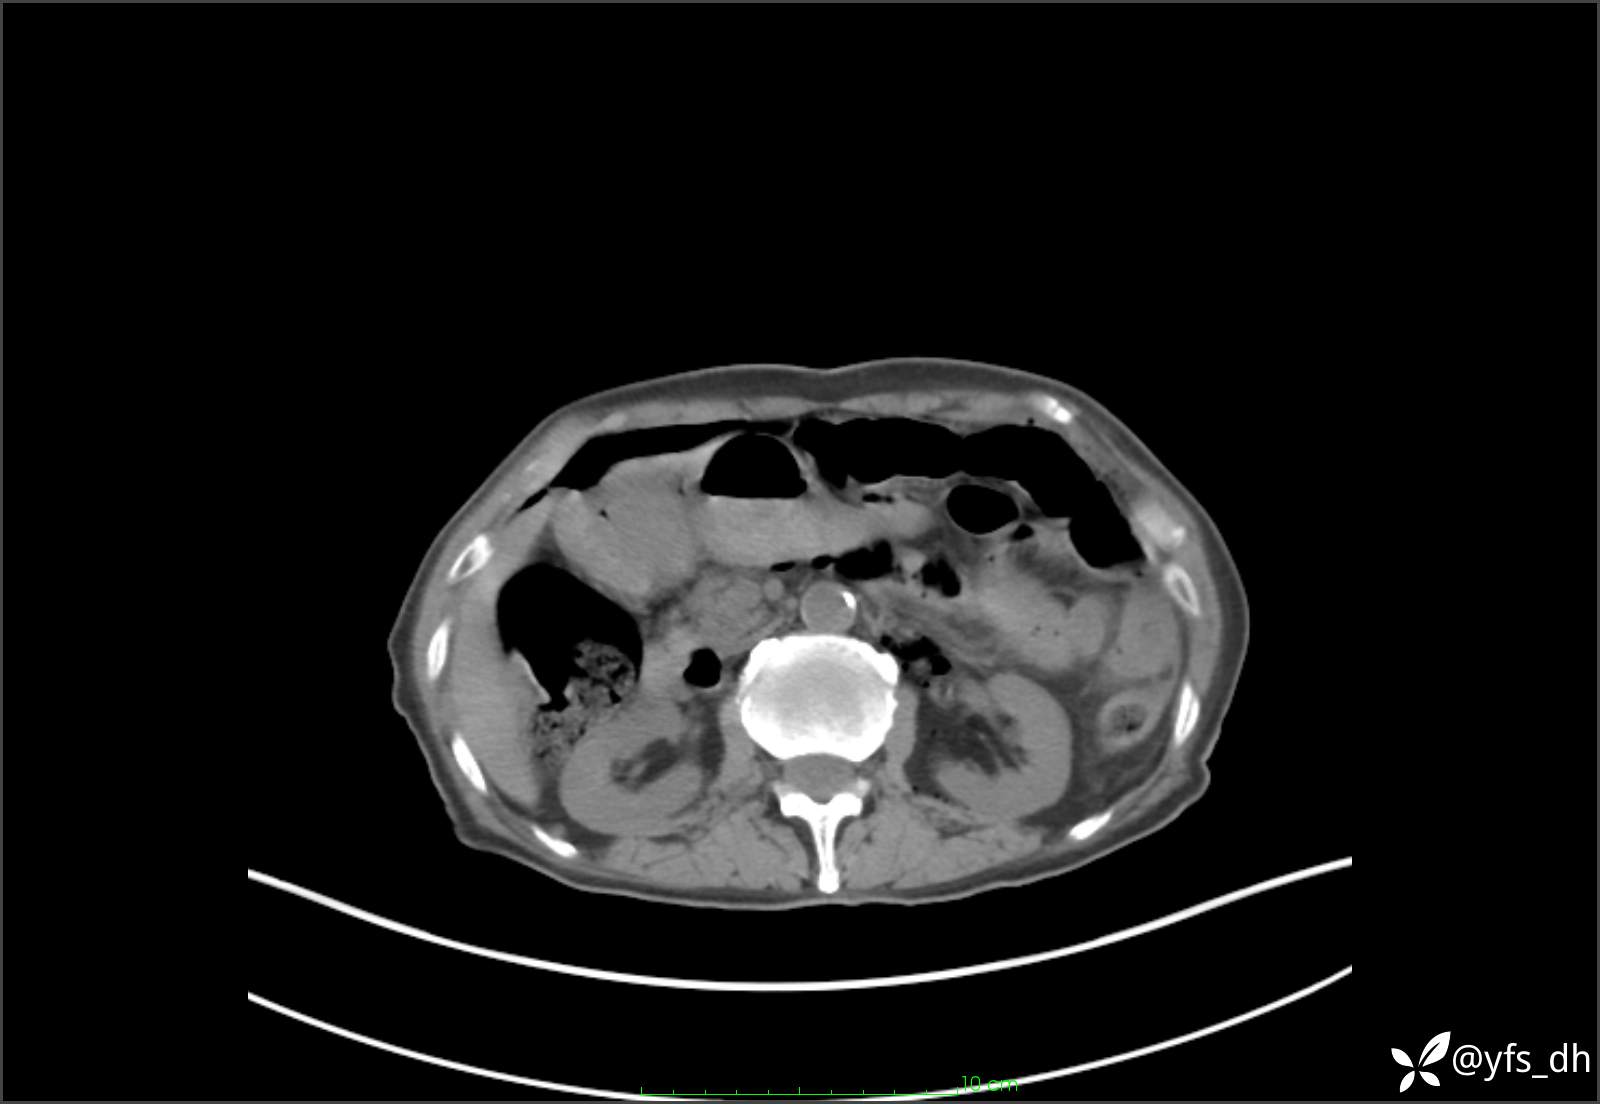

1.简要病史:患者4天前突发上腹部疼痛不适,但可以忍受。3小时前饭后突然加重,不能忍受后就诊。

2.简要手术记录:术中见腹盆腔大量肠液及粪便,乙状结肠中下段见一约3cm的破口。